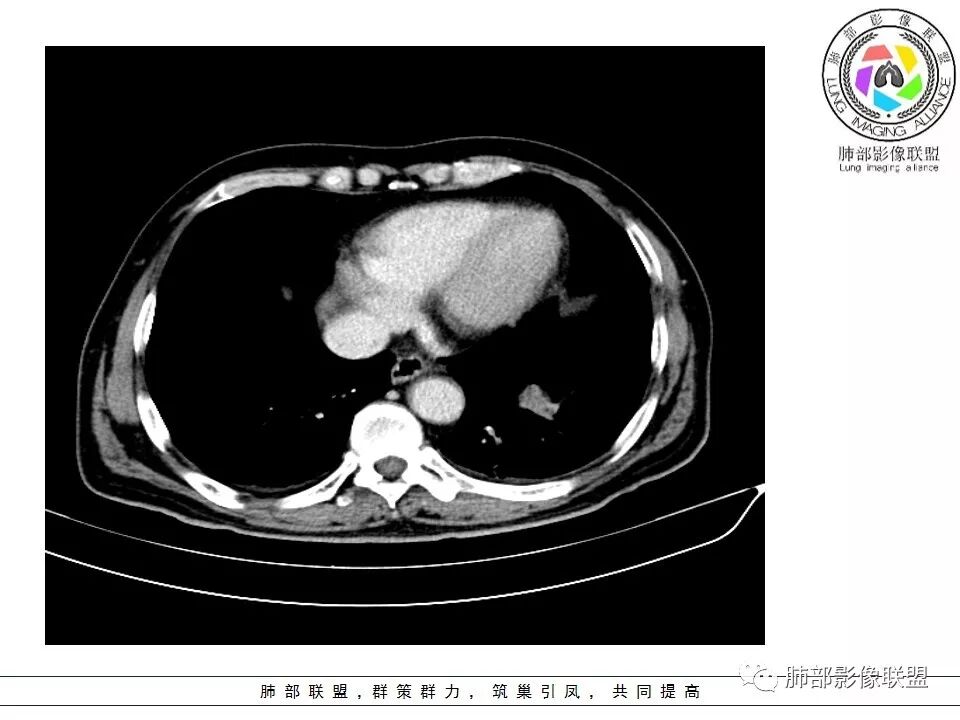

恶性没问题吧  ,哪位老师标示一下病灶

那些是淋巴结?哪是主病灶?

支气管如何?肺动脉?肺静脉?

南边:我发一个图

南边:这病灶与支气管啥关系啊?

南边:与肺静脉啥关系?这样追下去是不是很恶啊

南边:病灶分为两大块,外围囊实性大肿块,支气管关系不密切,内带多发淋巴结,侵犯支气管、肺血管,恶性没问题,按理间叶为主,或不典型的癌,这不是一个中央型的肺癌,是外朝内进展的,奇怪的是边界这么清楚光滑,一般癌肉瘤、肉瘤类多,其次才是癌,远端也没有阻塞,大方向是这样,恶性,间叶来源?或者混合,恶性程度较高,鉴别就是结核,因为结核是妖

1.左肺下叶近肺门区肿块,肿块外围大,内带小,提示外围向中央生长,符合周围型SCLC沿支气管方向生长。

2.病灶边缘光滑,未见明显分叶、毛刺,符合神经内分泌癌、癌肉瘤及间叶来源肿瘤。

3.病灶内密度偏低,穿行血管未见明显异常,轻度不均匀强化,为乏血供病灶。病灶内可疑坏死区,未见空洞;乏血供符合SCLC,但坏死区不符合。

4.病灶区支气管以受压推移为主,管腔不规则,腔内通而不畅,提示病灶粘膜下为主,符合SCLC迁徙蔓延或间叶来源肿瘤。

5.病灶内有血管走行,血管局部受压,但是强化考虑为乏血供,提示病灶内肺动脉并不是供血血管,只是病灶侵袭性强把血管包埋而已,为血管包埋征;血流面光滑,血管包埋符合SCLC。

6.左肺门淋巴结肿大,与病灶局部融合分界不清,呈冰冻肺门;而纵隔内未见肿大淋巴结,冰冻肺门符合SCLC,但是病灶主体那么大,纵隔内没有明显肿大淋巴结,不是很符合SCLC娘小崽大的特点。

7.未见明显阻塞性炎症及阻塞性肺不张,更加提示病灶从外围向中央侵犯,符合SCLC罕见阻塞性肺不张。